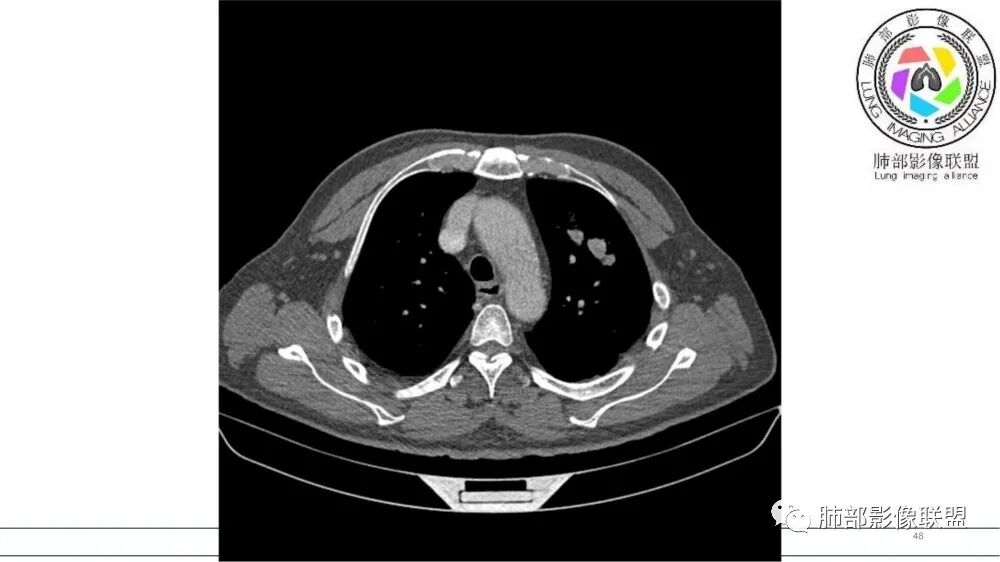

左肺上叶前段支气管内铸形生长软组织影,增强后均匀强化,远侧见斑片状磨玻璃影。考虑恶性病变,粘表?粘液腺?

老年男性,左肺上叶前段支气管内铸形阴影,增强后病灶不均匀强化,内部有坏死?远端可见斑片状阴影(阻塞性肺炎)。考虑恶性病变,老年人,鳞?类癌?粘表不能排除。

男,70岁,吸烟史,咳嗽,胸闷憋气一个月,左肺上叶不规则形软组织密度影,病灶沿支气管走形,周围见粟粒及棉絮样稍高密度影,增强扫描病灶内见少许坏死,考虑鳞癌可能,鉴别结核。

老年男性,肺气肿,吸烟史,左肺上支气管腔内铸型高密度影,呈指套状,远端多发树芽,增强不均匀强化,考虑鳞癌,鉴别小细胞癌

B3指套征,常规不是鳞癌就是ABPA,有强化丶血管造影征,倾向于鳞癌

老年男性,长期吸烟史。左上肺前段沿支气管走形的指套样病变,增强可见病灶强化(排除结核、ABPA(也无气喘症状)),远端多发点状高密度影。考虑恶性肿瘤,鳞癌可能性大。

指套征,扩张支气管内软组织强化,远侧肺野阻塞性炎,纵隔、左肺门肿大淋巴结;老年男性,吸烟,考虑鳞癌,鉴别小

指套征:是影像征象,胸部平片表现为手指状密度增高影,以肺门为中心呈放射状分布,CT显示扩张支气管内低密度黏液栓形成或实性病变,呈管状、树枝状或卵圆形密度增高影;支气管扩张伴近端梗阻时,扩张支气管内部黏液分泌物不能排出而形成。可以伴随远端空气潴留征、阻塞性炎症。